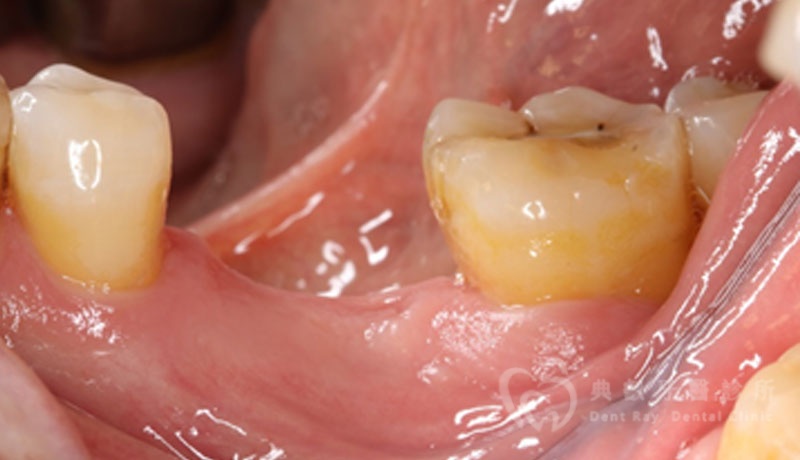

植牙案例一

植牙案例